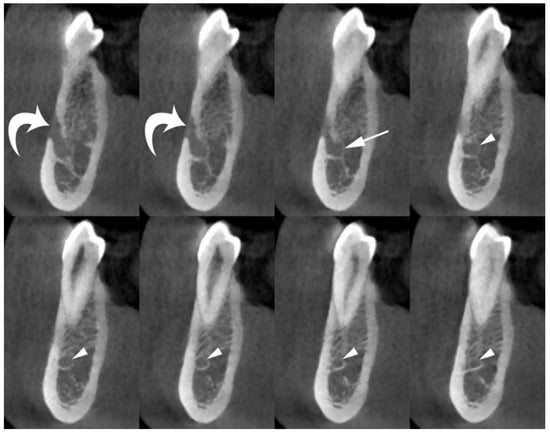

The acquired volume was reconstructed as axial images with a voxel size ≤ 200 µm. Using a dedicated tool for dental planning, this high-resolution dataset was further reconstructed as multiplanar images (200-µm-thick), perpendicular to the curvature of the mandible (cross-sectional images). Cross-sectional images are the most appropriate reconstructions to evaluate the presence and size of the MIC and its relationships with the adjacent mandibular anatomical landmarks (Figure 2).

Figure 2.

Cross-sectional CBCT images show the origin and position of the MIC (arrowheads) within the spongiosa of the mandible, and its relationships with adjacent anatomical landmarks (cortical plates and first premolar apex). The mental foramen (curved arrows), and anterior loop of mandibular canal (arrow) are also shown.